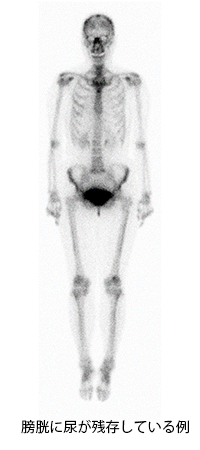

全身の骨の状態を見る検査です。この検査は、午前中に検査用の薬を注射します。撮像は午後行います。撮像時間は約30分です。使用する薬は、主に尿中に排泄されるため、尿がたまっていると膀胱周辺の骨の情報がわかりにくくなります。そのため、撮影直前にお手洗いに行っていただきます。